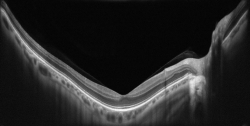

AVANTİ Optik Koherens Tomografi (OCT)